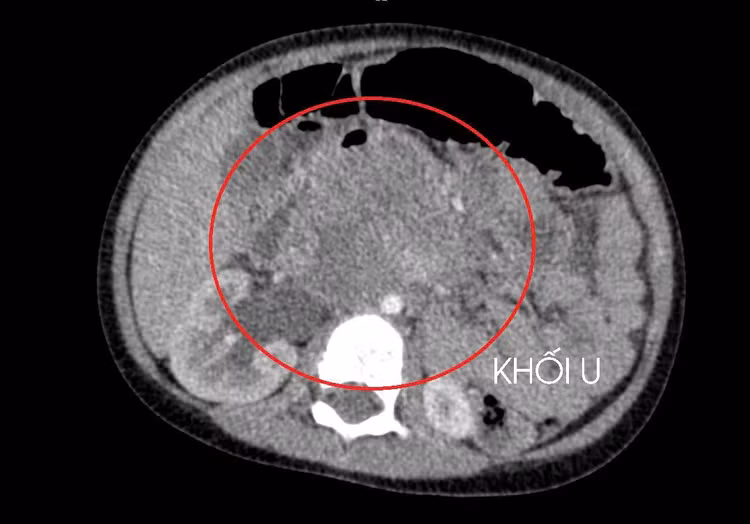

Qua thăm khám lâm sàng, chụp cắt lớp vi tính ổ bụng và siêu âm, các bác sĩ phát hiện một khối u lớn sau phúc mạc, chèn ép thận. Sau quá trình đánh giá toàn diện, kết quả cho thấy bé mắc ung thư tinh hoàn, theo dõi di căn gan và phổi.

Khối u ung thư do tinh hoàn ẩn - Ảnh BVCC